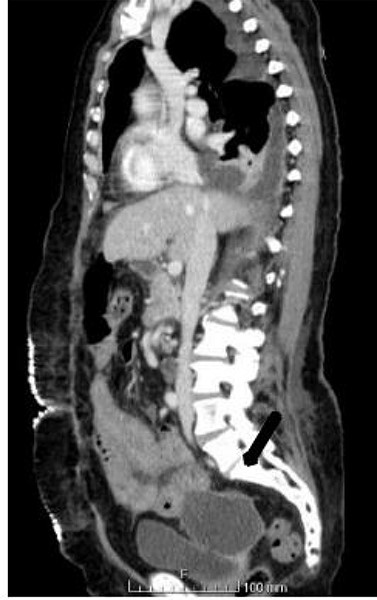

An abdominal computed tomography (CT) scan was performed, which identified an internal hernia at the root of the right mesentery, an apparent abscess in the right lung base (65 × 55 mm) (Fig. 1) as well as elevation of the right diaphragmatic hemi-dome with Chilaiditi sign (Fig. 2).